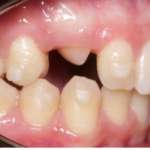

Presentiamo il caso di una paziente adulta in cui è stato eseguito un trattamento ortodontico con meccanica asimmetrica mediante apparecchiatura ortodontica linguale 2D. L’obiettivo: ottenere la correzione secondaria di una malocclusione caratterizzata da agenesia degli incisivi laterali superiori e di un premolare inferiore, associata ad affollamento dentale terziario a entrambe le arcate; al trattamento è seguita riabilitazione implanto-protesica di uno degli incisivi laterali agenesici.